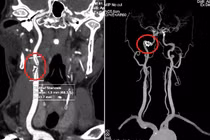

Qua các bước khám lâm sàng và chẩn đoán hình ảnh, người phụ nữ được phẫu thuật xử lý túi phình, cứu sống trong tình huống nguy hiểm.